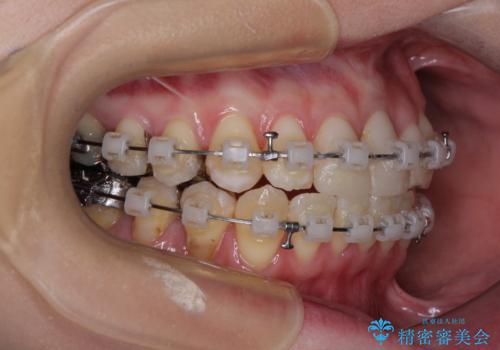

- 矯正装置

- クリアブラケット

- 前歯のデコボコとセラミッククラウン周りの黒い縁を気にして来院された患者様です。

ワイヤー装置、マウスピース、どちらの装置でも治療は可能でしたが、マウスピース矯正の自己管理の煩わしさを懸念され、ワイヤー装置にて矯正治療を行うこととしました。

前歯の黒い縁は、矯正治療後にオールセラミッククラウンにて改善することとしましたが、いち早く目立たなくしたいとのことで、事前に矯正治療用仮歯に置き換えてから矯正治療を開始しました。

前歯を早々に仮歯に置き換えたことで、矯正治療に意欲的に臨んでくださいました。

口元が前方に突出することもなく、綺麗に仕上げることができました。